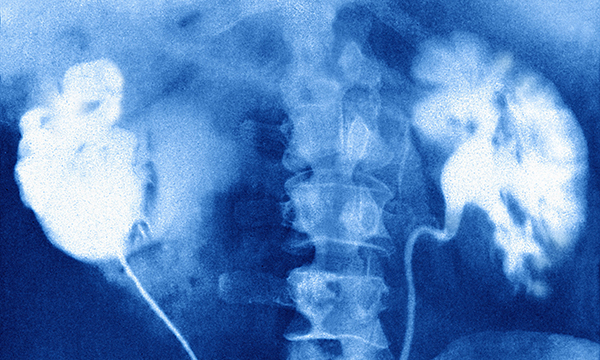

Acute kidney injury, previously referred to as acute renal failure, is a common and often preventable condition that is seen in patients in acute and primary care settings. Nurses in both settings should be able to identify and assess patients at risk of acute kidney injury, and those with developing acute kidney injury, and understand the principles of clinical management. Early identification can assist in prevention of acute kidney injury, while supportive management and interventions can prevent further deterioration in patients diagnosed with the condition. This article describes acute kidney injury and outlines the pathophysiology, staging, and signs and symptoms. The author also describes the clinical management of patients with acute kidney injury and the long-term effects of the condition.